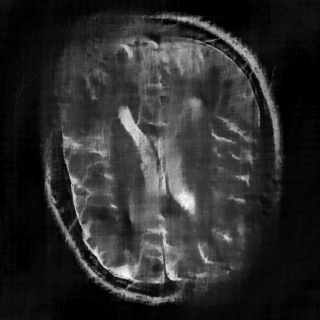

This article presents a novel undersampled magnetic resonance imaging (MRI) technique that leverages the concept of Neural Radiance Field (NeRF). With radial undersampling, the corresponding imaging problem can be reformulated into an image modeling task from sparse-view rendered data; therefore, a high dimensional MR image is obtainable from undersampled $k$-space data by taking advantage of implicit neural representation. A multi-layer perceptron, which is designed to output an image intensity from a spatial coordinate, learns the MR physics-driven rendering relation between given measurement data and desired image. Effective undersampling strategies for high-quality neural representation are investigated. The proposed method serves two benefits: (i) The learning is based fully on single undersampled $k$-space data, not a bunch of measured data and target image sets. It can be used potentially for diagnostic MR imaging, such as fetal MRI, where data acquisition is relatively rare or limited against diversity of clinical images while undersampled reconstruction is highly demanded. (ii) A reconstructed MR image is a scan-specific representation highly adaptive to the given $k$-space measurement. Numerous experiments validate the feasibility and capability of the proposed approach.